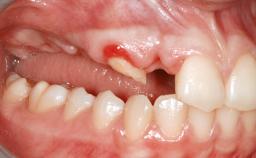

A 45-year-old woman with a completely edentulous maxilla was referred to evaluate the possibility of rehabilitation with an implant-supported prosthesis. This patient was healthy and a non-smoker. She had been wearing a maxillary complete denture opposing a natural mandibular dentition since her twenties. This situation had resulted in progressive resorption of the alveolar ridge, repeatedly creating a need for relining the denture. Twenty years later, despite multiple adaptations and the use of “glues” the denture was unstable and causing the patient psychological and functional discomfort.

Bone Volume Horizontally and vertically sufficient Horizontally deficient Deficient vertically or deficient vertically AND horizontally

Bone Volume Deficient vertically or deficient vertically AND horizontally